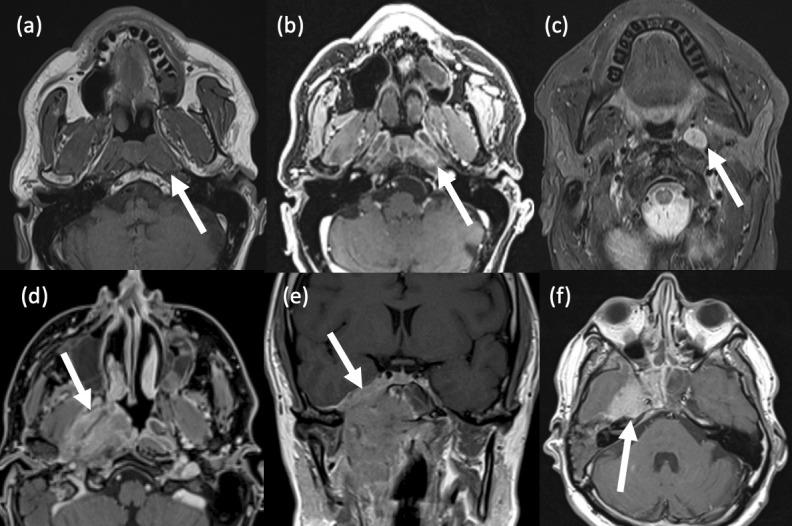

咽病理学的影像学表现。

Imaging of pharyngeal pathology.

The pharynx plays a significant role in swallowing and speech, and this is reflected in both its complex anatomy and degree of physiological motility. Patients who present with pharynx-related symptoms such as sore throat, globus, dysphagia or dysphonia will usually undergo visual and nasal endoscopic examination in the first instance. Imaging is frequently required to supplement clinical assessment and this typically involves MRI and CT. However, fluoroscopy, ultrasound and radionuclide imaging are valuable in certain clinical situations. The aforementioned complexity of the pharynx and the myriad of pathologies which may arise within it often make radiological evaluation challenging. In this pictorial review, we aim to provide a brief overview of cross-sectional pharyngeal anatomy and present the radiological features of a variety of pharyngeal pathologies, both benign and malignant.

咽在吞咽和言语中起着重要作用,这反映在其复杂的解剖结构和生理运动程度上。出现咽痛、咽部异物感、吞咽困难或发音困难等咽部相关症状的患者通常首先进行视诊和鼻内镜检查。影像学检查常需要补充临床评估,通常包括 MRI 和 CT。然而,透视、超声和放射性核素成像在某些临床情况下具有重要价值。上述咽的复杂性和可能发生的多种病理改变常常使影像学评估具有挑战性。在本影像学综述中,我们旨在简要概述咽的横断解剖结构,并介绍各种良性和恶性咽病变的影像学特征。